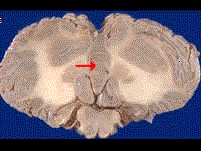

如图箭头所示为小脑哪个部位 ( )A、小脑扁桃体B、小脑中脚C、小脑下脚D、小脑蚓部E、小脑上脚

问题 如图箭头所示为小脑哪个部位 ( )

选项 A、小脑扁桃体 B、小脑中脚 C、小脑下脚 D、小脑蚓部 E、小脑上脚

答案 D